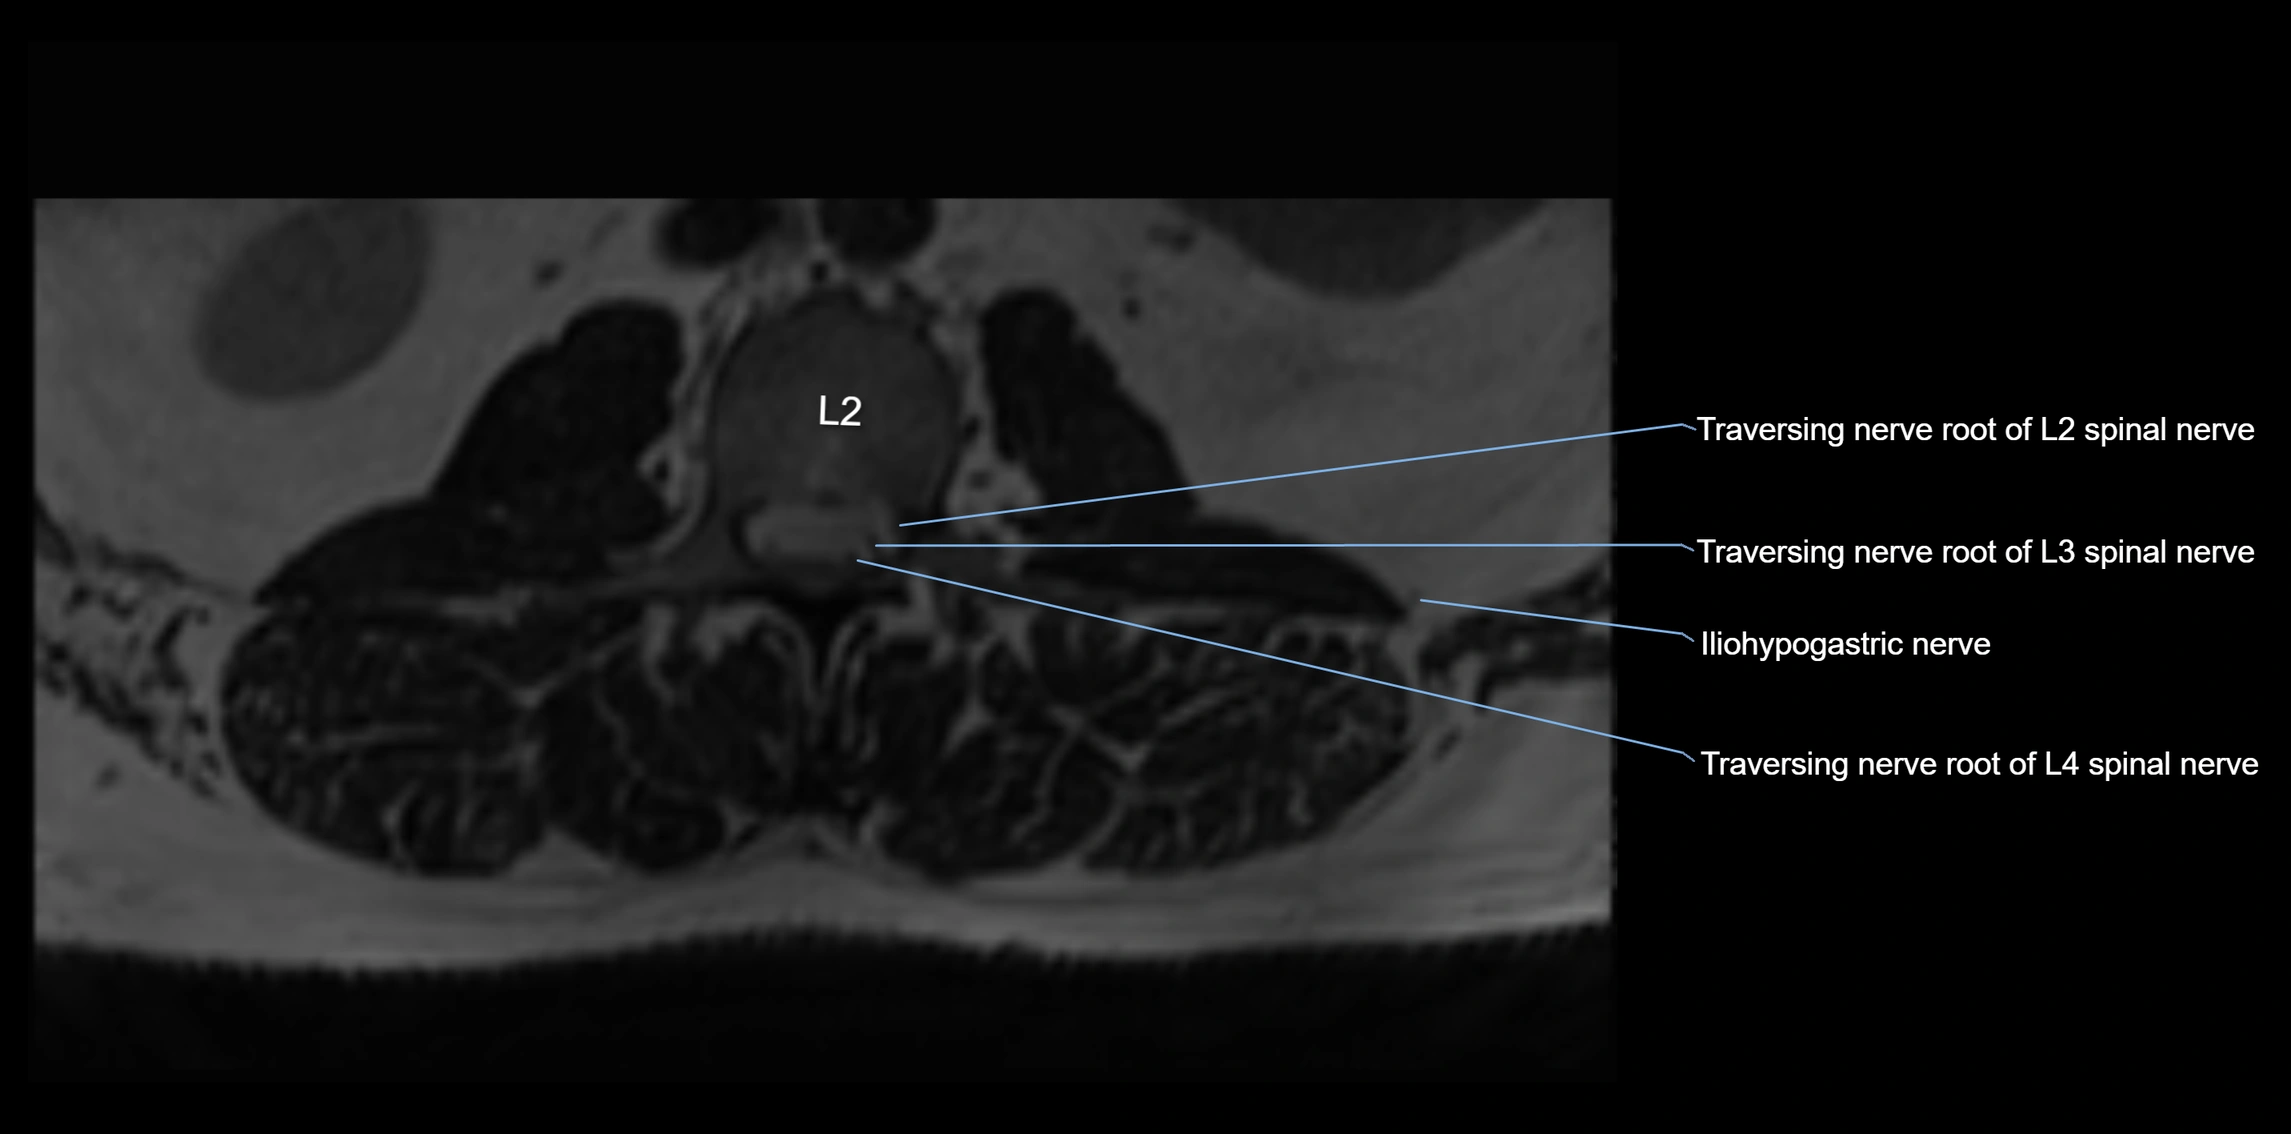

MRI Appearance

T1-weighted images:

• Nerve appears as a very thin low-to-intermediate signal intensity structure

• Surrounded by bright fat, aiding visualization

T2-weighted images:

• Nerve shows intermediate to mildly hyperintense signal compared to muscle

• Pathological involvement appears brighter

STIR (Short Tau Inversion Recovery):

• Normal nerve appears dark

• Inflamed or entrapped nerve appears bright hyperintense

T1 Fat-Sat Post-Contrast:

• Normal nerve enhances minimally

• Pathologic nerve (neuritis, entrapment, tumor infiltration) shows focal or diffuse enhancement

3D T2 SPACE / CISS:

• Nerve appears intermediate to mildly hyperintense compared to muscle

• Surrounded by bright fat or CSF, improving visualization

• Best sequence for mapping small pelvic nerves such as the anococcygeal

MRI image

image